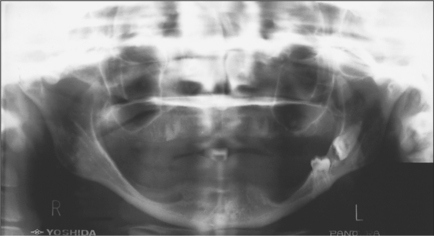

Contraindications to removal

where there is an increased risk of significant complications, e.g. a high risk of permanent inferior alveolar nerve damage or fracture of the mandible (Fig. 5.10).

image

Fig. 5.10 A severely resorbed mandible. The horizontal third molar and impacted second molar occupying the full depth of the mandible show an increased risk of jaw fracture. (Note retained roots in the maxilla.)